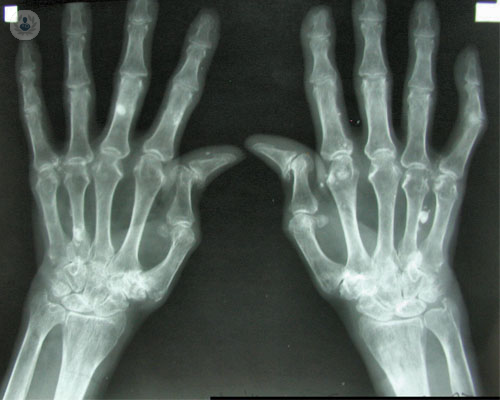

¿Cuáles son las causas y el diagnóstico de la artritis reumatoide?

No se conoce la causa exacta de la artritis reumatoide, pero se piensa que debe ser la consecuencia de la acción de un agente ambiental actuando sobre un organismo susceptible determinado, portador de determinadas características genéticas.

Tratamiento de la artritis psoriásica en las manos

La artritis psoriásica afecta a las articulaciones de los dados, influyendo en su movilidad. La traumatóloga Dra. Esplugas expone el tratamiento para esta enfermedad.